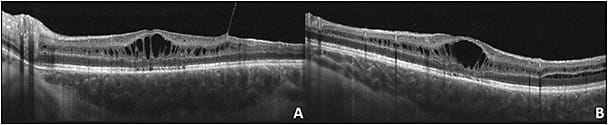

X-linked retinoschisis (XLRS) was first described by Joseph Haas in 1898.1 It is a congenital retinal dystrophy caused by a mutation in the retinoschisin (RS1) gene, located on Xp22.1, which encodes for retinoschisin protein that functions in cellular adhesion.2 The most characteristic clinical finding is foveal schisis cavities with a spoke-wheel pattern in the neurosensory retina with or without peripheral schisis (Figure 1).1,3,4 Spectral-domain optical coherence tomography (SD-OCT) findings in XLRS include foveal cystoid spaces with splitting of the inner nuclear layer (INL) and outer plexiform layer (OPL).5

Imaging findings with SD-OCT of the fovea (Figure 1) showed cystic maculopathy in all included eyes. Cysts were found in the inner nuclear layer in all eyes, outer plexiform layer in 4/11 (36%) eyes, outer nuclear layer in 5 (45%) eyes, and ganglion cell layer in 1 (9%) eye. In all 11 eyes there was distortion of the vessel architecture in the superficial capillary plexus. In 9 eyes, there was no appreciable foveal avascular. In all cases, there were avascular cystic cavities surrounded by vessels in a petaloid-like shape in the deep retinal plexus. There were no telangiectatic vessels or aneurysmal dilations identified. The choriocapillaris was within normal limits in 11/11 eyes (Table 1).